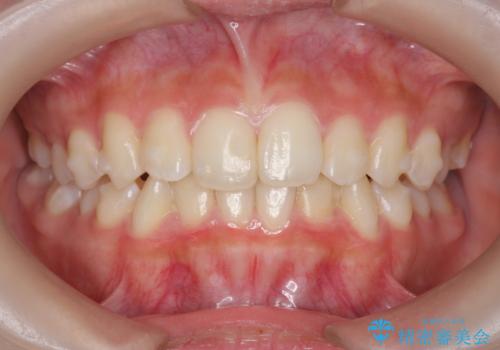

インビザラインライトで行う短期マウスピース矯正治療

- 前歯のガタつきを並べたいたいと、矯正治療を希望され来院されました。

とにかく短期間で前歯だけの治療を行いという希望が強く、全体矯正と前歯だけの部分矯正の仕上がりのイメージを確認したのち14枚のマウスピースで前歯のみの矯正治療を行っていくこととしました。

インビザラインライトは軽度なガタつきや傾斜の改善に用いられる全14枚のマウスピース矯正です。

短期間で治療の終了が見込めるだけでなく、料金もインビザラインフルに比べリーズナブルです。